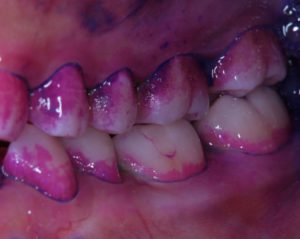

まずはバイオフィルムを分かりやすくするために赤く染め出しを行います。染出しを行うことで、歯ブラシが当たりにくい所が明確になります。